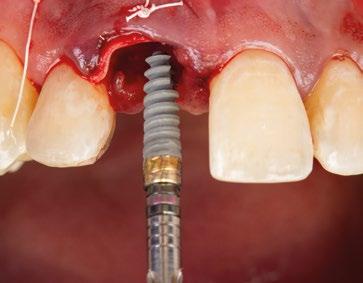

10.- Colocamos implante Nobel Biocare N1TM TiUltra de 3,5x13. (Figura 26)

11.- Observamos el torque obtenido de 50N por lo tanto podemos realizar carga inmediata. (Figura 27)

12.- Colocamos aditamento N1TM Base XealTM con el fin de trabajar la prótesis a nivel gingivall. (Figura 28)